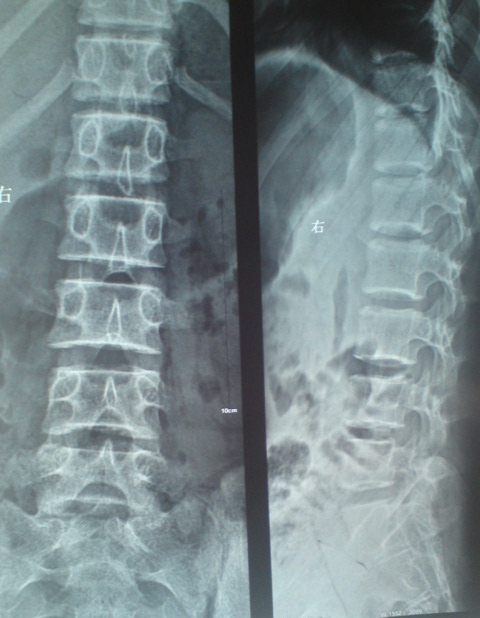

标题: CT27836:女 ,13岁,腰痛数月,加重一月,检查下腰部明显压 [打印本页]

标题: CT27836:女 ,13岁,腰痛数月,加重一月,检查下腰部明显压

考虑腰椎结核,建议做椎体扫描。

考虑腰4椎体结核伴右侧椎旁及椎管右侧硬脊膜外脓肿形成。

建议椎体扫描连续层面观察或mri看看,是脓肿还是软组织肿块,tb脓肿很少到后方来的,肺部有无tb灶。